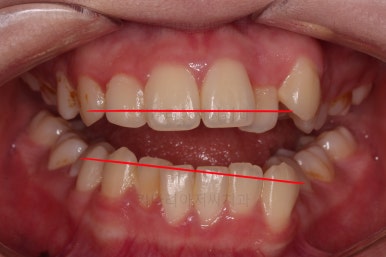

그리고 선을 그려놨는데 윗니의 라인과 아랫니의 라인이 평행이 아니죠.

기울어 있어서 양측의 교합의 강도가 다른 상황이었습니다.